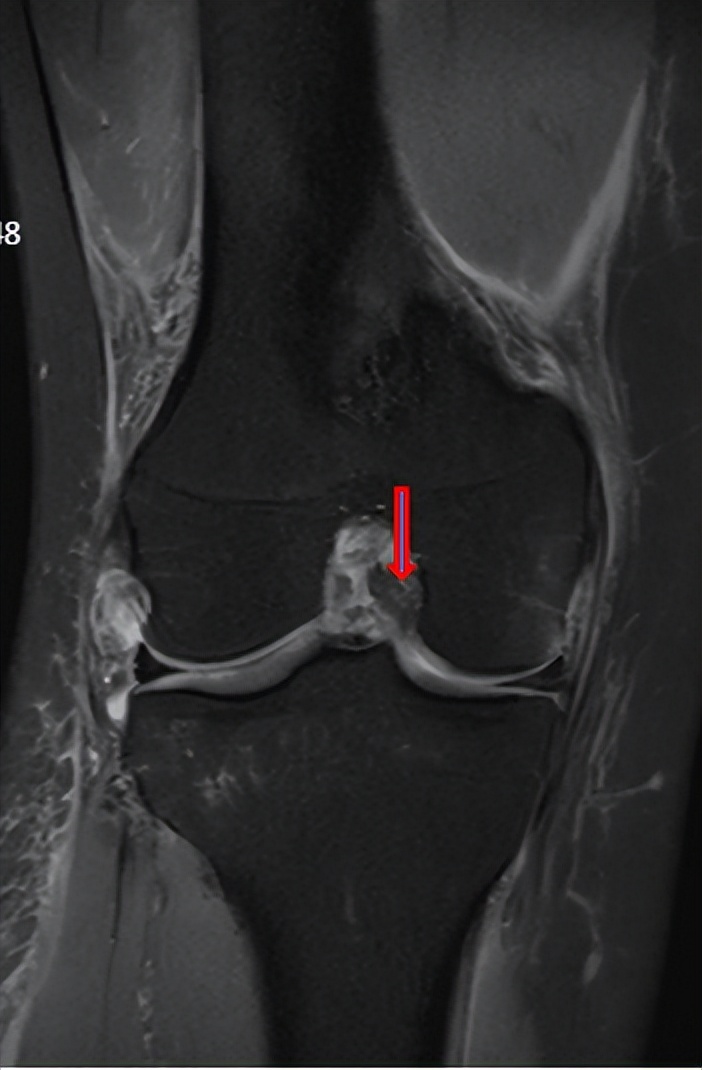

△术前可以看到前交叉韧带断裂

经过几番辗转,烦恼的小张了解到,广东省第二人民医院关节骨科有运动医学方面的专家,便特意来到广州就诊。广东省第二人民医院关节骨科运动医学组组长何河北医生对她进行了详细查体,认为这不是普通的扭伤,而是 左膝关节前交叉韧带断裂 ,需要及时进行手术治疗。

何河北医生告诉小张,膝关节前交叉韧带断裂在生活中很常见,特别是 在打篮球进行疾跑急停转向等动作时容易发生 。针对这样的情况,建议进行关节镜下微创治疗,使用自体肌腱重建韧带,手术创伤小,术后疼痛轻微,康复较快。